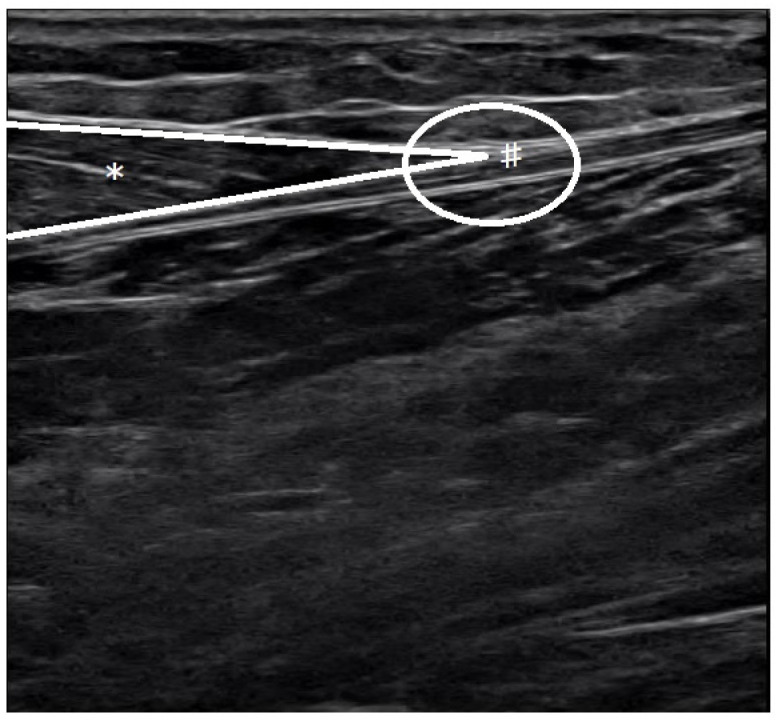

Methods: This study included 23 men who underwent ultrasound imaging to measure the Achilles tendon length while they stood on an inclined table adjusted according to the dorsiflexion angle. Treadmill walking was performed for 10 min with a 10° incline (gradient condition) or without gradient (level condition). The measurements were compared using a paired t-test.

Results: In the gradient condition, the range of motion for ankle dorsiflexion was significantly increased after the intervention. In the gradient condition, the Achilles tendon length while standing on an inclined surface was significantly increased after the intervention.